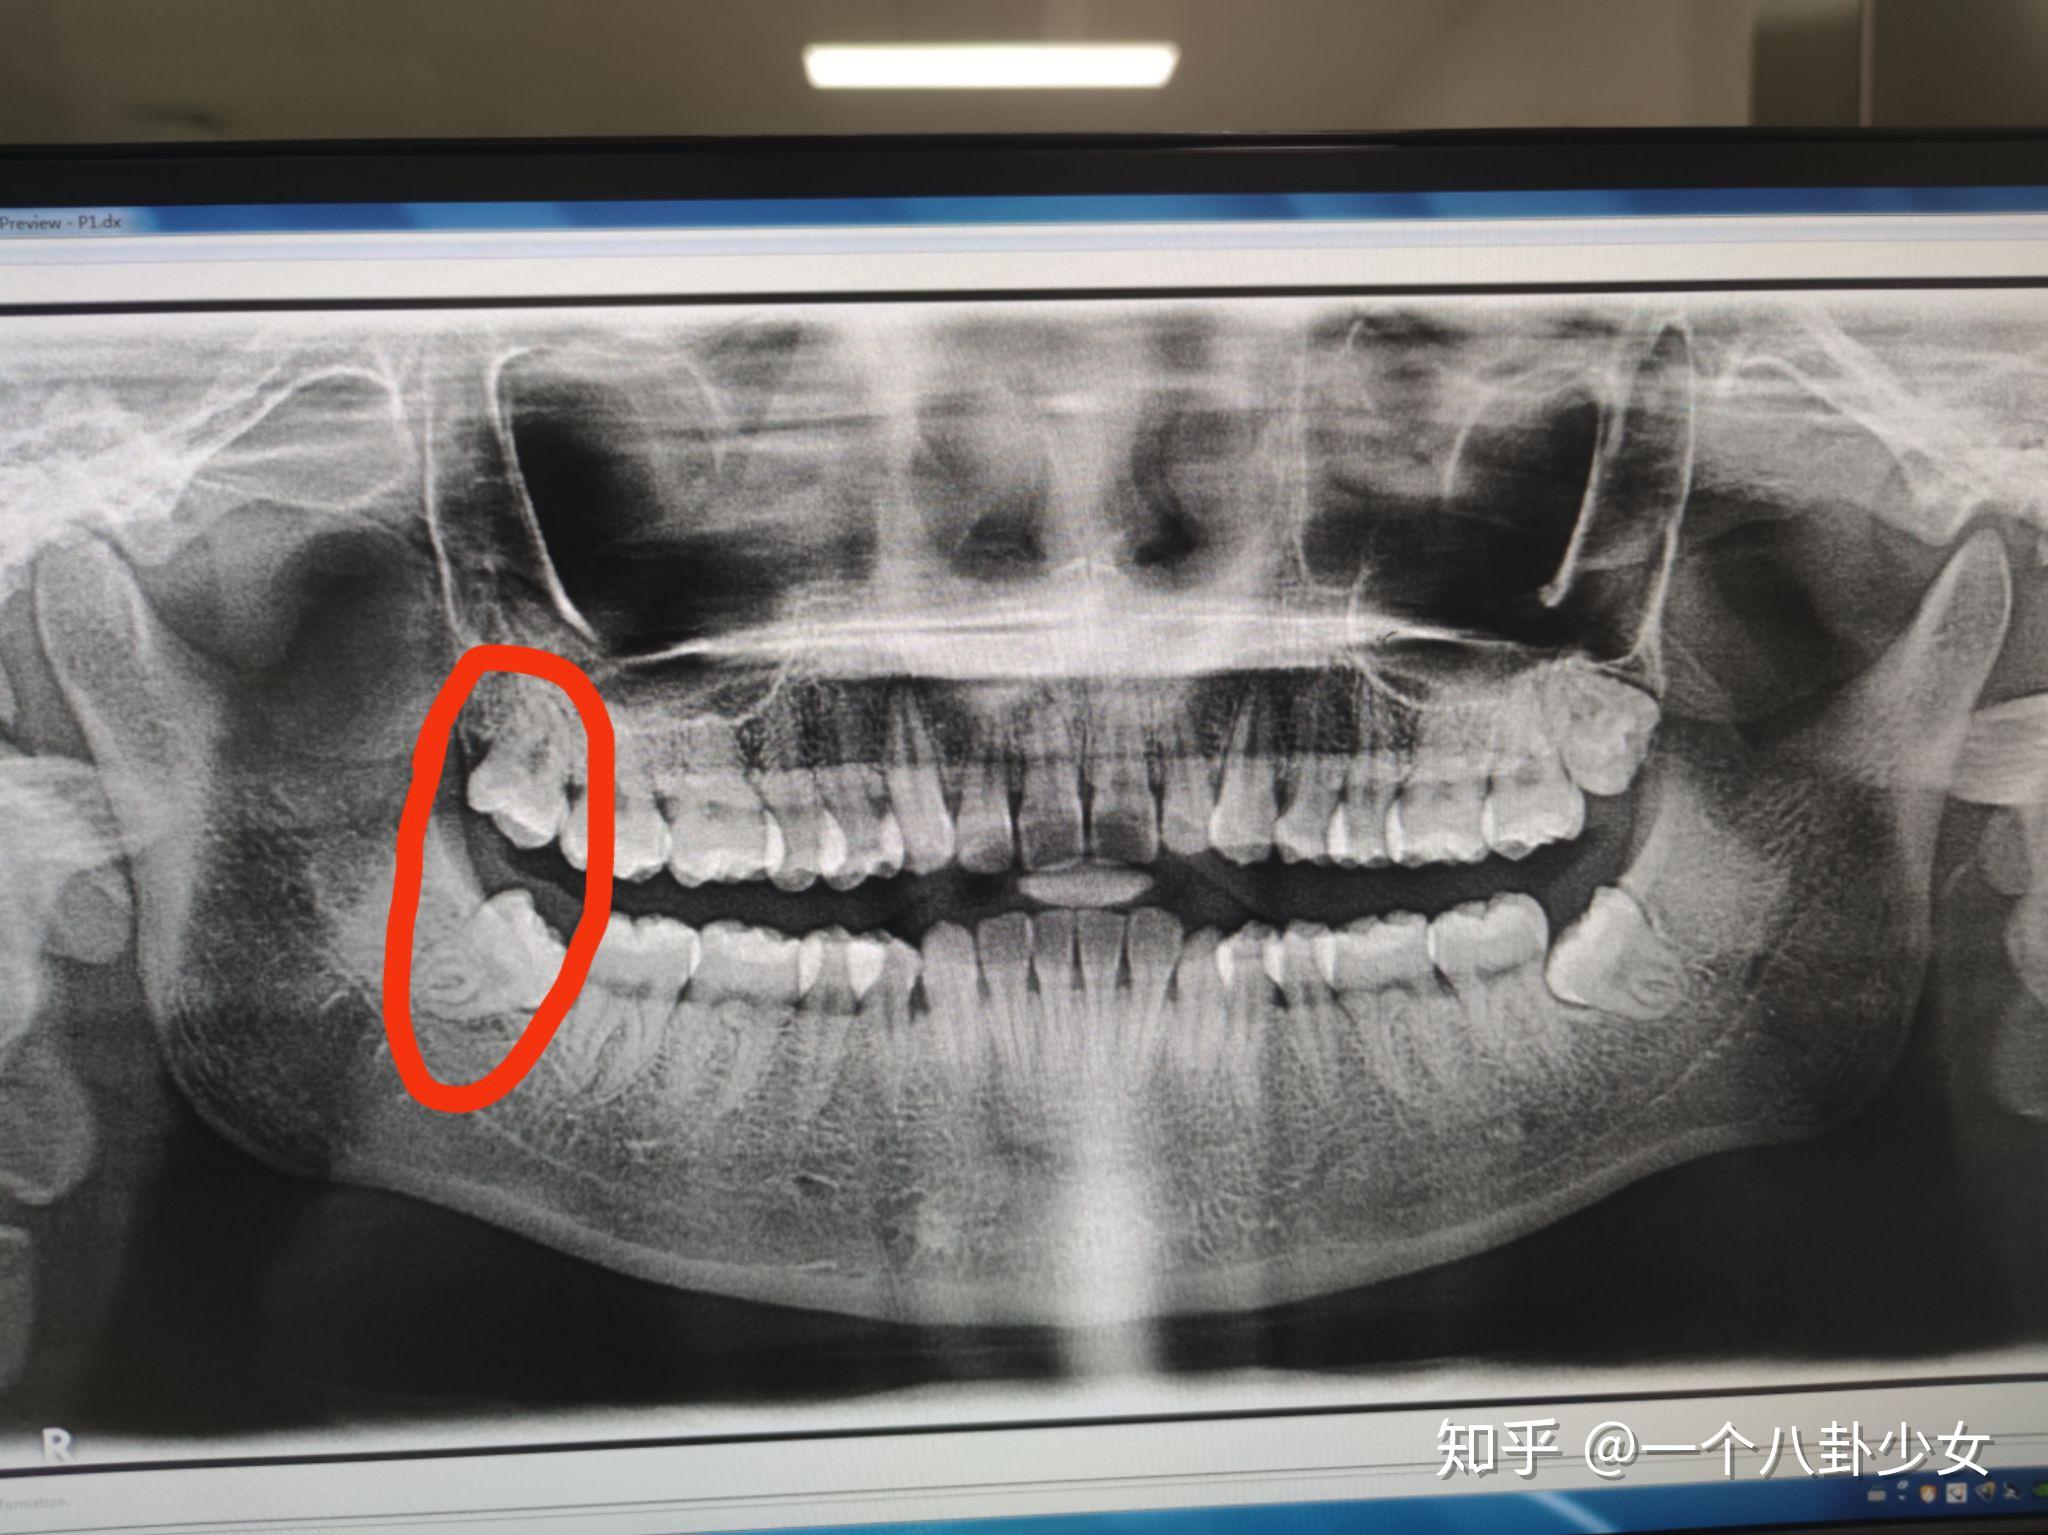

滚吧讨厌的智齿

图片尺寸640x512